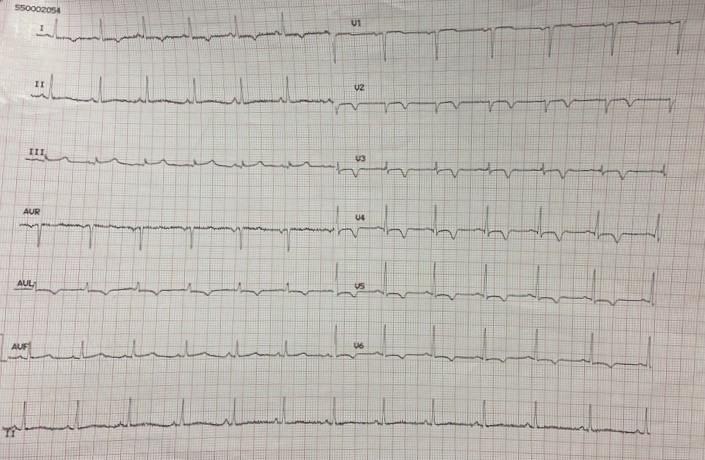

The ECG conducted in the emergency department (Fig. 2 — admission ECG) revealed sinus tachycardia with a heart rate of 103 beats per minute. Poor progression of the R wave in the precordial leads was observed along with minimal ST segment elevation from V1 to V3 in the context of widespread ventricular repolarization abnormalities.

Fig. 2.

Fig. 2.Admission ECG showing sinus tachycardia with a heart rate of 103 beats per minute. Poor progression of the R wave in the precordial leads was observed along with minimal ST segment elevation from V1 to V3 in the context of widespread ventricular repolarization abnormalities. ECG, electrocardiogram.

During the hospitalization, the patient experienced the recurrence of similar episodes of mild chest pain; all of them occurred after minor exertion, lasted a few minutes and were self-resolving. The 12 leads ECG performed during the last one of them showed few changes: biphasic T waves with initial positivity and terminal negativity in leads V2 and V3 slightly resembling type A Wellens pattern were present (Fig. 4 — ECG).

Fig. 4.

Fig. 4.ECG showing biphasic T waves with initial positivity and terminal negativity in leads V2 and V3 slightly resembling type A Wellens Syndrome. ECG, electrocardiogram.

A few minutes later, the patient experienced a further episode of chest pain, which occurred at rest, but was of greater intensity and duration, and had no clear triggering factors, another 12-lead ECG was performed and showed some differences compared to previous recordings: symmetrically inverted T waves were evident in leads V2 and V3, this time resembling a type B Wellens pattern (Fig. 5 — ECG). As discussed above, these ECG patterns, in a patient admitted for chest pain with slightly elevated serum cardiac markers and negative 3-hour hs-troponin T delta, should raise suspicion of Wellens Syndrome, which is highly specific for critical stenosis of the LAD.

Fig. 5.

Fig. 5.ECG showing symmetrically inverted T waves in leads V2 and V3, resembling a type B Wellens pattern. ECG, electrocardiogram.